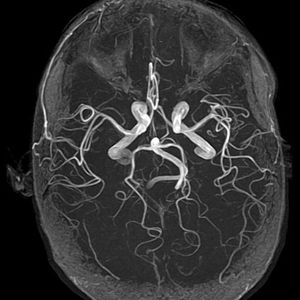

Circle of Willis MRA

MRA (Magnetic Resonance Angiography) of the Circle of Willis - anastomotic system of arteries that sits at the base of the brain.